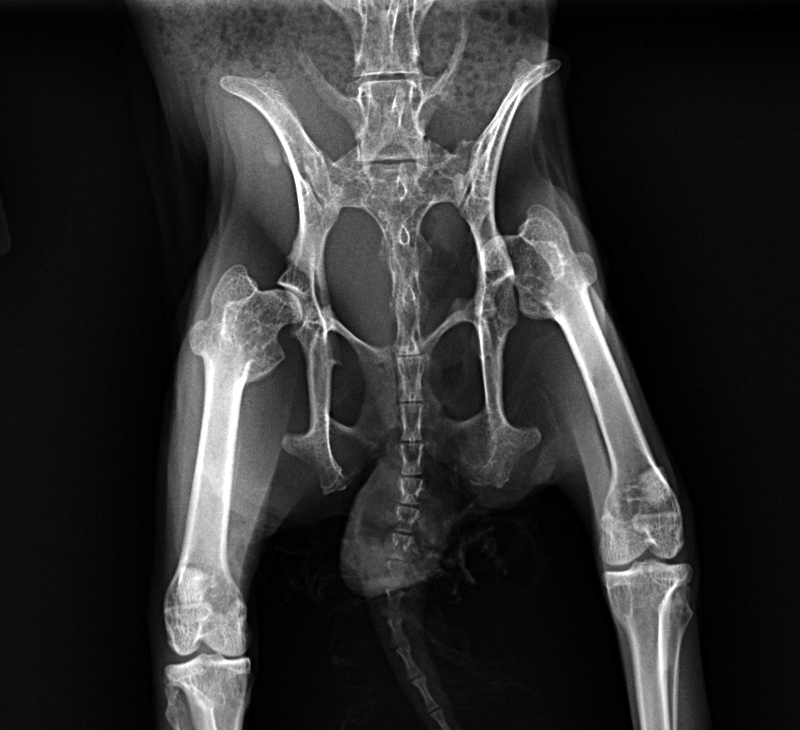

From 2010vets.blogspot.com

Veterinary, Photography and Travel Stories for vet students and pet Can A Cat Walk On A Dislocated Hip If your cat has a dislocated joint, it needs to be looked by a veterinarian in order to get a proper diagnosis and treatment. Hip dislocation, from hip dysplasia or from injury,. If you suspect your cat has a dislocated joint, it is important to seek veterinary care immediately to prevent further damage and ensure proper. When the round ligament. Can A Cat Walk On A Dislocated Hip.